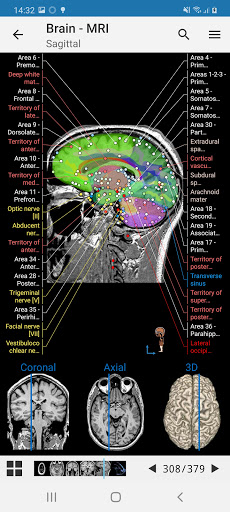

تصوير الأوعية الدماغية بالرنين المغناطيسي: اختبار عادي على تباين الطور MRV

- وحدتان جديدتان: الدماغ - TOF والأوعية الدموية الدماغية ، أطلس التشريح الوعائي العصبي الطبيعي لشرايين الدماغ على الأوعية الدموية الدماغية. - تم إعادة صياغة الواجهة. - تتوفر علامة تبويب جديدة باسم "QuickLinks" ، ترسل وحدات في أقسام من جسم الإنسان وتسمح لك بالسفر السريع إلى الوحدات التي تبحث عنها. الخلل الصغيرة الثابتة.